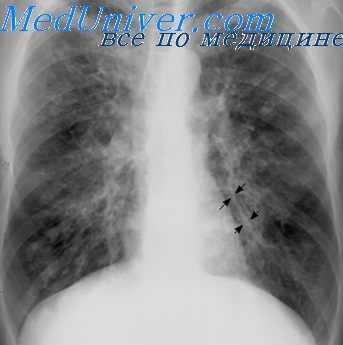

На прямой и боковой проекции рентгенограммы легких у пациентов с бронхоэктатической болезнью обнаруживаются деформация и ячеистость легочного рисунка, участки ателектазов, уменьшение в объеме пораженного сегмента или доли. Эндоскопическое исследование бронхов – бронхоскопия – позволяет выявить обильный, вязкий гнойный секрет, взять материал на цитологию и баканализ, установить источник кровотечения, а также провести санацию бронхиального дерева для подготовки к следующему диагностическому этапу – бронхографии.

Бронхография (контрастное рентгенологическое исследование бронхов) является самым достоверным диагностическим методом при бронхоэктатической болезни. Она позволяет уточнить степень распространенности бронхоэктазов, их локализацию, форму. Бронхография у взрослых пациентов проводится в под местной анестезией, у детей – под общим наркозом. С помощью введенного в бронхиальное дерево мягкого катетера происходит заполнение бронхов контрастным веществом с последующим рентгенологическим контролем и серией снимков. При бронхографии выявляется деформация, сближение бронхов, их цилиндрические, мешотчатые или веретенообразные расширения, отсутствие контрастирования ветвей бронхов, расположенных дистальнее бронхоэктазов. Для диагностики степени дыхательной недостаточности пациенту с бронхоэктатической болезнью проводят исследования дыхательной функции: спирометрию и пикфлоуметрию.